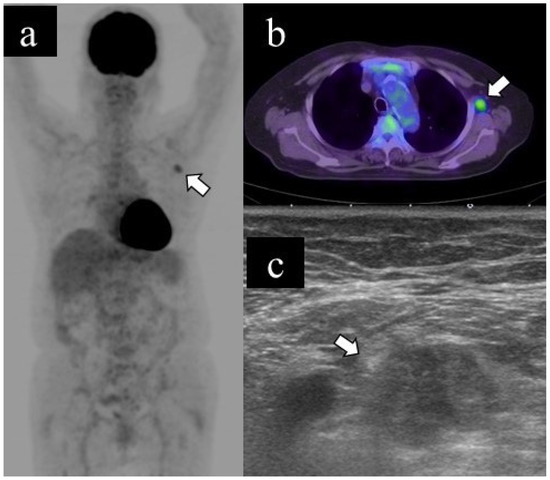

Figure 2 and Figure 3 show representative cases of benign and malignant lymphadenopathy, respectively.

The patient, in her 60s, had cutaneous sarcoidosis and underwent a PET scan as a screening test. The results showed lymphadenopathy and abnormal uptake throughout the body, including the left axillary lymph node (a. b, arrow). US examination revealed left axillary lymphadenopathy (long diameter: 25.2 mm, short diameter: 8.9 mm, cortical thickness: 4.1 mm, and presence of fatty hilum) (b, arrow); subsequently, she underwent US-guided CNB. The pathological diagnosis was sarcoidosis. Spontaneous shrinkage of the lymph nodes was observed on follow-up.

Figure 2. Representative case of benign lymphadenopathy. (a) Maximum-intensity projection (MIP), (b) transaxial 18F-FDG PET/CT image and (c) US image of benign lymphadenopathy.